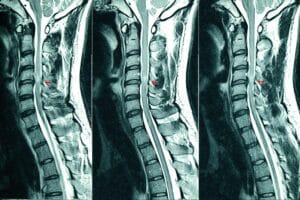

Imaging, such as X-rays or MRIs, may be ordered if necessary:

- MRI: Provides detailed images of the spinal cord, nerves, and discs to identify nerve compression or herniated discs.

Please note that if you are having a spinal injection, then you will need to have an up to date MRI scan that has been done within the last 6 months. We can help arrange these for you if they are required.

- Diagnostic Ultrasound: For diagnosing cervical radiculopathy, MRI and CT scans are typically preferred as they provide detailed images of the spine, nerves, and surrounding structures. However Ultrasound allows for real-time, dynamic imaging, enabling clinicians to assess nerve mobility and muscle function during specific movements. This can help differentiate between radicular pain originating from the cervical spine and other causes of neck or arm pain.

While ultrasound is not a definitive diagnostic tool for cervical radiculopathy, it can complement other diagnostic methods, particularly for assessing soft tissue changes and guiding treatment such as spinal injections.